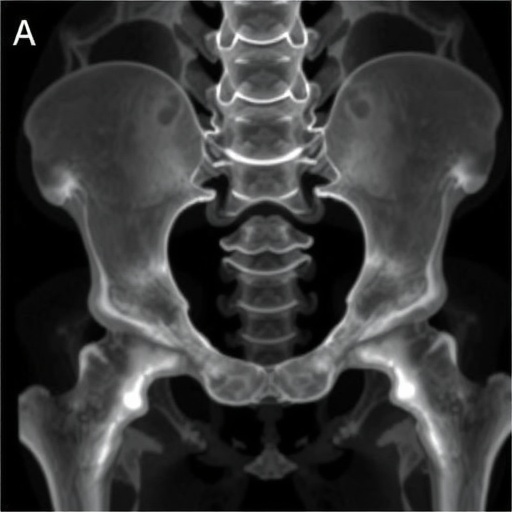

Technologically, this study harnesses cutting-edge imaging modalities like 3D computed tomography scans and digital segmentation tools, which allow for unprecedented visualizations and measurements of complex pelvic anatomy. The digital morphometric approach surpasses traditional manual measurements by reducing observer bias and improving reproducibility—essential qualities in forensic science where standardization is paramount.

The researchers embarked on a systematic examination of a large osteological sample, employing advanced morphometric analyses to quantify asymmetries present in the acetabular regions. Morphometric assessments, which involve precise measurements of size and shape, have revolutionized anatomical studies by providing quantitative frameworks beyond subjective visual assessments. Through statistical rigor, the team discerned patterns that defy the notion of perfect bilateral symmetry, highlighting a directional tendency—meaning the asymmetry shows a predictable side preference rather than occurring randomly.